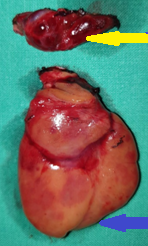

Purple arrow: over-descended large superior parathyroid adenoma. Yellow arrow: normal right inferior parathyroid gland found in the thymothyroid ligament (Courtesy Dr. V. Penopoulos)